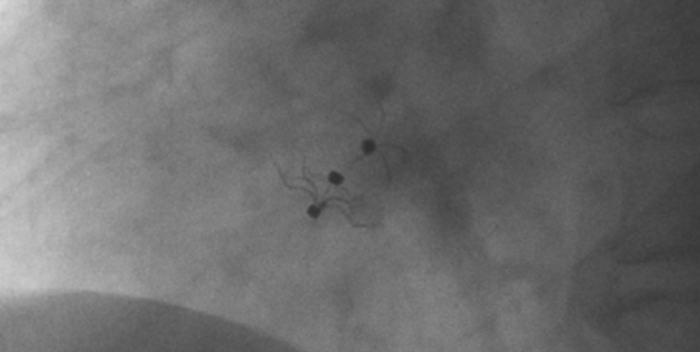

影像顯示試驗器械適應性貼合于房間隔兩側且穩定

術中造影顯示患者為PFO且長隧道型,目前市場上已商業化的PFO封堵器難以滿足該患者解剖結構封堵需求。迪創醫療自主研發的OmniSeal PFO封堵器自適應性雙盤貼合設計能廣泛適應不同PFO隧道長度的解剖結構和形態,其雙盤外包覆式阻流和隧道內填充阻流相結合的雙重阻流設計,可為此患者實現有效封堵。與此同時,OmniSeal首創的完全可穿刺式設計,也為此患者最大程度地保留了房間隔區域穿刺通道,以實現全兼容未來可能的左心系統二次介入術。術終造影和心臟超聲顯示封堵完全、效果良好。作為OmniSeal的首例臨床應用,本次手術的順利完成和優異效果充分體現了產品的設計創新優勢。

迪創醫療自主研發的OmniSeal PFO封堵器系統具有多項創新設計和技術優勢,并且對于目前市場商業化產品的多個臨床痛點問題,如難以開展左心系統二次微創介入手術、術后新發心房顫動、殘余分流、血栓形成等器械相關的限制和并發癥等,提供了針對性的解決方案。OmniSeal PFO封堵器系統獨創的完全可穿刺式設計,能實現全兼容左心系統二次介入術。其較高的適應性使得產品可以適應不同卵圓孔未閉解剖學結構和形態,并減少對房間隔的刺激, 降低術后心律失常事件。同時,雙盤外包覆式阻流和隧道內填充阻流相結合的創新結構在確保有效封堵的情況下,減少殘余分流,降低血栓形成。